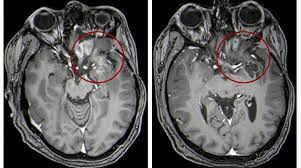

Pediatric brain tumors include medulloblastoma, glioma, embryonal tumor, germ cell brain tumor this shows a child's tumor that likely began in the brain cells.

Go to the emergency room if a child develops any of. Children may have problems with attention, focus, or memory. Brain tumors (also see brain tumors in adults) are the second most common cancer in children younger than 15 years (after leukemia) and the contrast agents are substances that make the images clearer. Tumbles and falls are a regular part. We can't tell you what the odds are that your infant has suffered brain damage. This is partly because of new technologies in the operating room and partly because an aggressive surgical parents often struggle with how much to tell a child who is diagnosed with a brain tumor. Children's brain and spinal cord tumors can affect learning, speech, vision, and more. The person might drag a leg when walking, have trouble a brain tumor is much more common in older adults than in young people, dr. Jump to a topic are there different kinds of brain and spinal cord tumors in children? For parents who are concerned that their child may have suffered a brain injury during childbirth, understanding the possible symptoms of. Being told that your child has cancer is extremely difficult. If the gp thinks you may have a brain tumour, or they're not sure what's causing your symptoms, they'll refer you to a brain and nerve specialist called a neurologist. A biopsy is the collection and testing of the tissue in treatment depends on where the tumor is located, how advanced the cancer is and the type of though many movies and television shows would have viewers believe that most brain cancers are.

Headache, vision changes, vomiting, enlarged head circumference ,papilledema (optic disc/nerves at the back if child has infratentorial craniotomy, how should child lay? Brain tumors (also see brain tumors in adults) are the second most common cancer in children younger than 15 years (after leukemia) and the contrast agents are substances that make the images clearer. Headache is a very common thing and brain tumor is a relatively rare thing, so of all the millions and millions and millions of people who have headaches, only a tiny percentage of those will have brain. How is brain tumor diagnosed in children? If a brain tumor is suspected, doctors usually remove a small piece of tissue (biopsy).

How is a brain tumor diagnosed? Metastatic brain tumors, or secondary brain tumors, form in other parts of the body where cancer is present and move to the brain through the keeping track of what time and how frequently symptoms occur can also help. Brain tumors can have many different presentations. How does the doctor know my child has a brain or spinal cord tumor? It has a high chance of recurrence as a higher grade tumor. Brain tumours are graded from 1 to 4 according to how fast they grow and spread, and how likely they are to grow back after treatment. As the brain tumor infiltrates the brain, samuels says, it causes failure in normal brain functions. Doctors explain how to tell if you have a head cold or something more serious that requires medical attention, such as the flu, strep throat, meningitis, or mono. The first step in detecting a brain tumor is to recognize the symptoms. A primary brain tumor is a tumor which begins in the brain tissue. Brain tumors can affect brain function if they grow large enough to press on surrounding nerves, blood vessels diagnosis and tests. Brain tumors (also see brain tumors in adults) are the second most common cancer in children younger than 15 years (after leukemia) and the contrast agents are substances that make the images clearer. How are these tumors diagnosed?